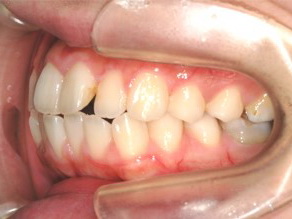

上顎の劣成長 (成長不足) による反対咬合で、上顎は拡大装置と上顎前方牽引装置を併用し前方方向への成長を促して前歯の咬み合わせを改善した後に、上下顎の前歯をマルチブラケット装置で並べました。治療の期間は2年でした。

初診時

1期治療終了時

2期治療終了時